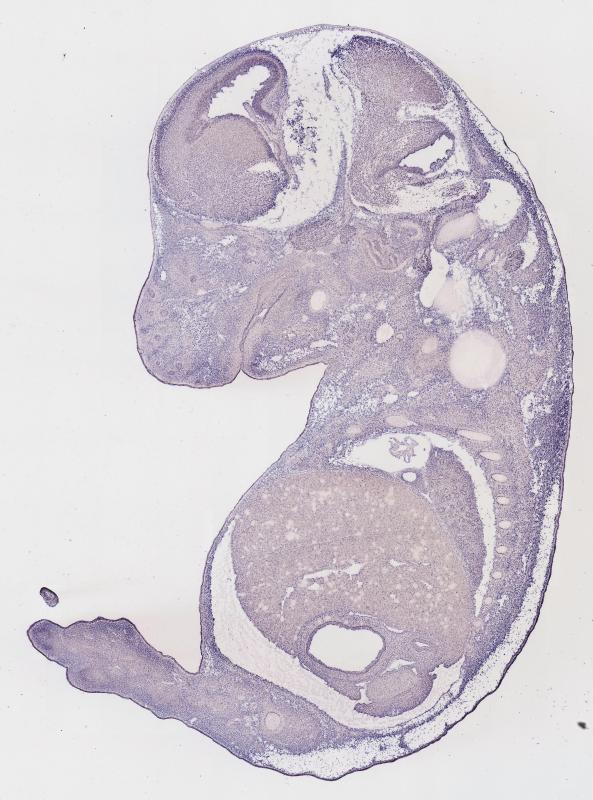

Specimen

MH837; Specimen C1251:

embryonic day 14.5